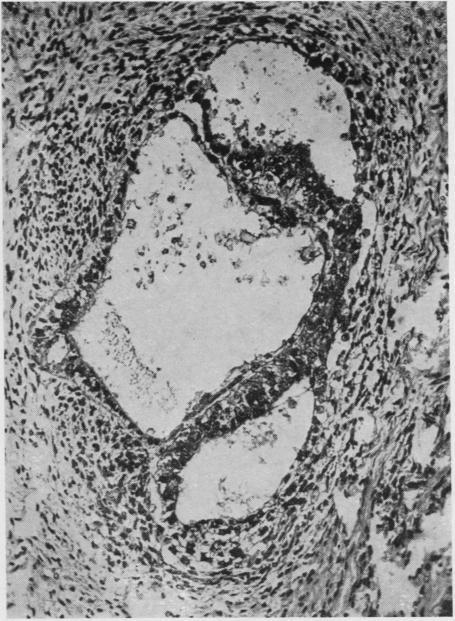

Developmental stages of embryo-like bodies in teratoma testis.